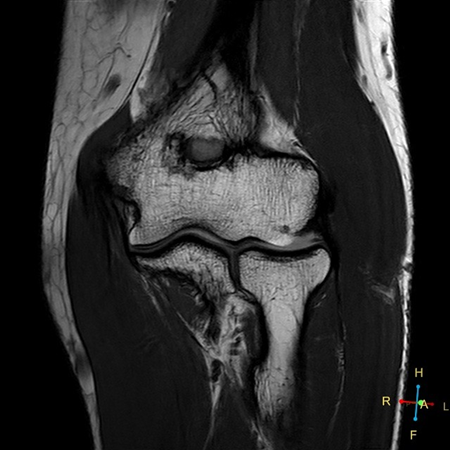

Coronal PDw TSE